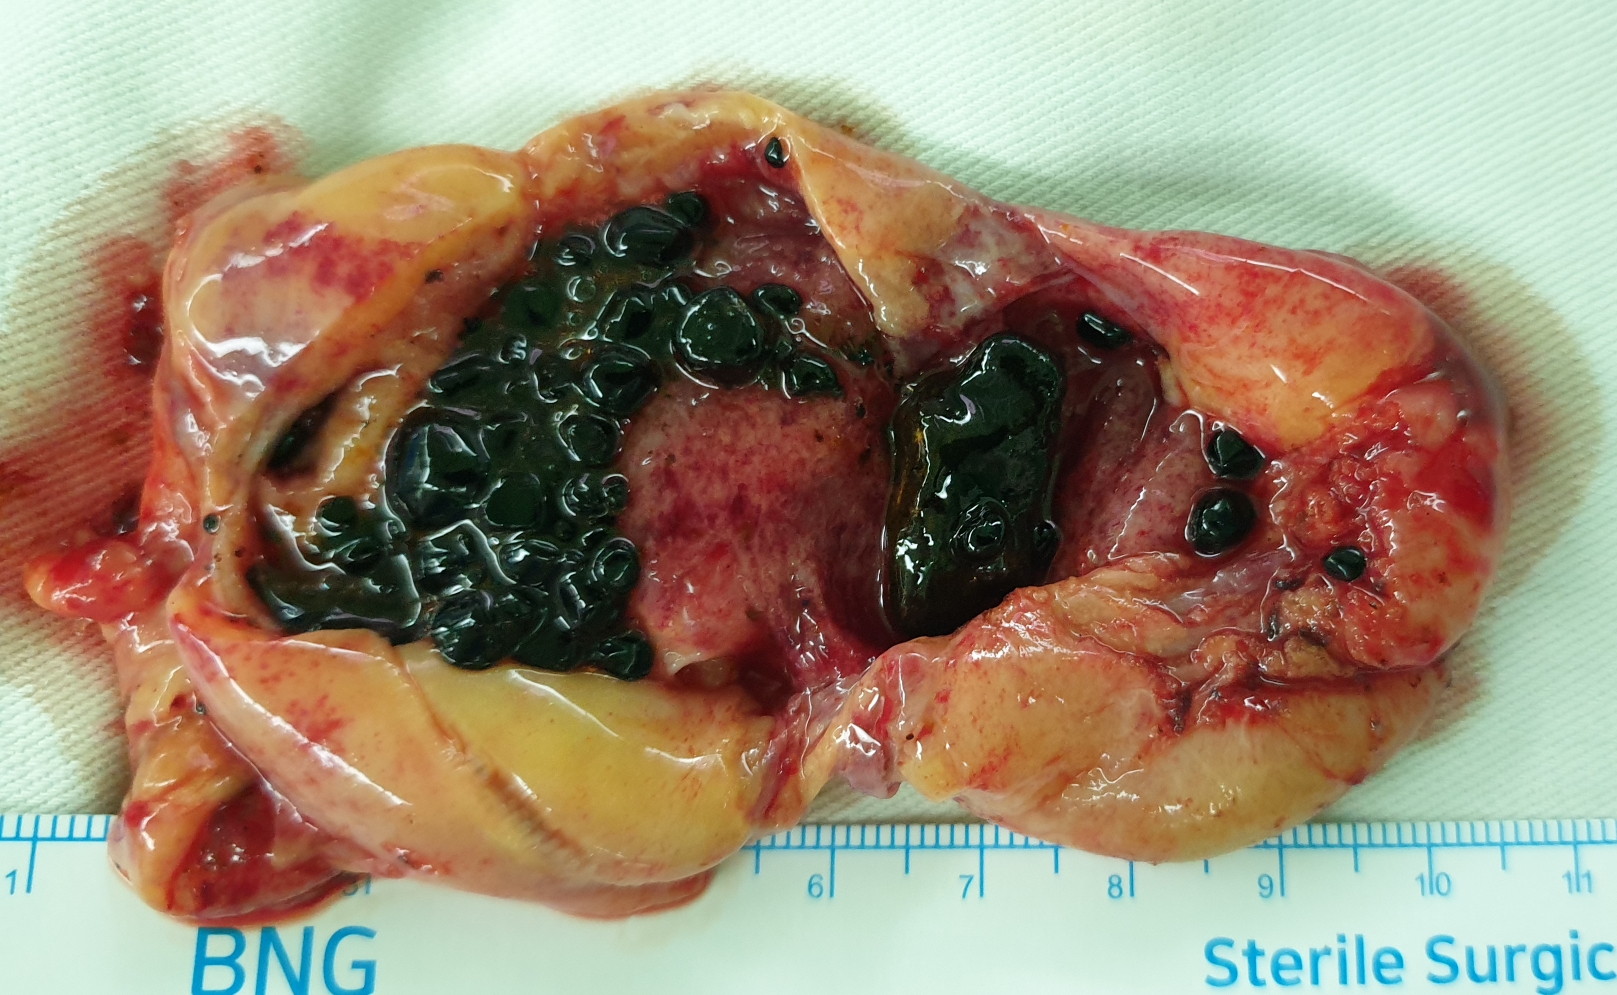

통증이 심해 어제 저녁 응급수술을 했습니다.

수술은 합병증없이 잘 끝났습니다.